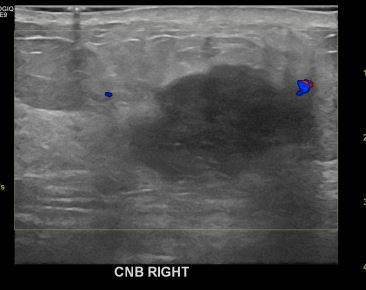

상기환자는 외부검진이상으로 내원하신 50대후반

여성분으로 의심스러운 우측혹 조직검사 시행해 침윤성암 으로 진단되었습니다